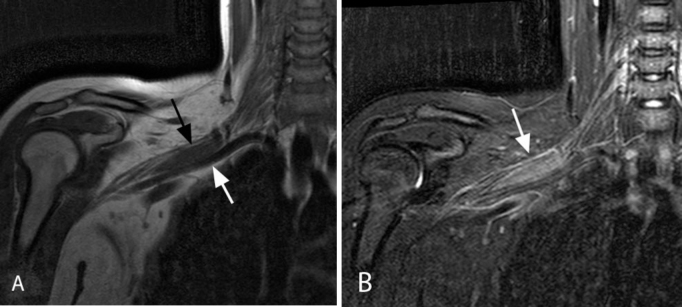

- 🔹 RM: es la técnica de elección. Muestra un engrosamiento fusiforme del nervio afectado, que puede medir varios centímetros de longitud. La señal es iso-hipointensa en T1 respecto al músculo, hiperintensa en T2/STIR y presenta realce homogéneo tras contraste.

RM representativa de perineurioma